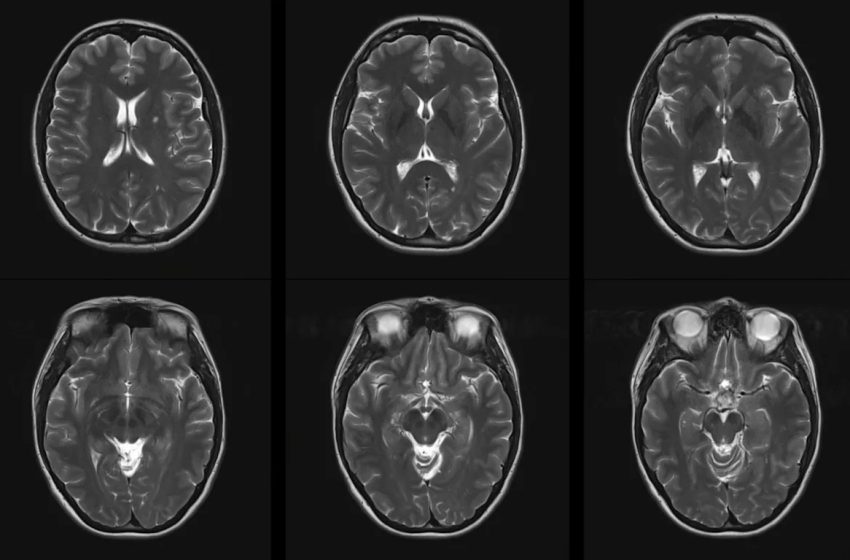

Short-term exposure to particulate matter and all of the other pollutants was linked to at least one, if not all, of the negative impacts like lesions, worsening disease, or heightened relapse risk.

“Our study provides strong evidence of the association between air pollution and risk of developing MS and severity of MS including relapses, developing CELs [contrast-enhancing lesions], and disability progression,” the scientists wrote.